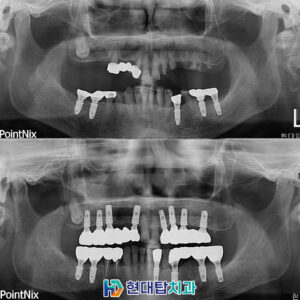

*모든 증례 사진은 의료법 제23조, 제 56조에 의거하여 환자분의 동의 하에 업로드가 진행되었습니다.

*치료 사진은 모두 본원에서 치료한 환자분의 사진입니다.

*치료 사진은 모두 동일인의 사진이며, 동일조건에서 촬영하였습니다.

*개인의 차이에 따라 시술 및 수술 후 부작용이 발생할 수 있으며, 의료진과 충분한 상담을 받으시기 바랍니다.